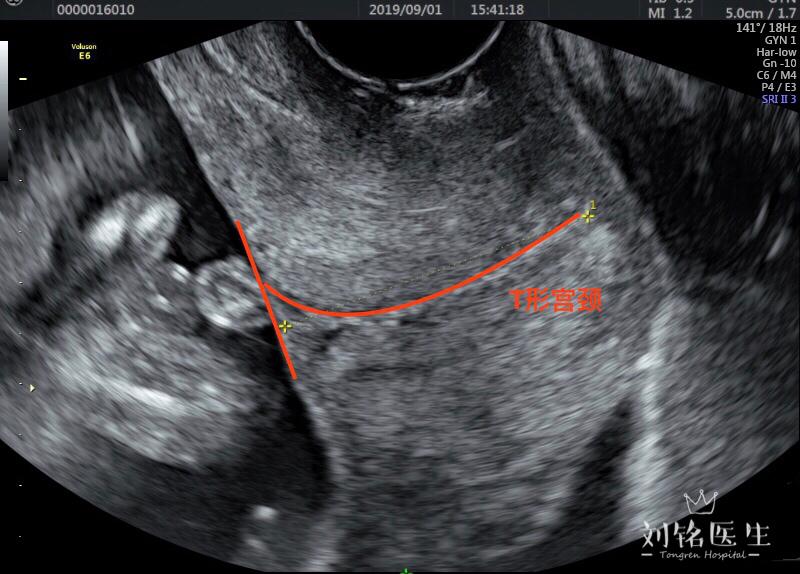

這是超聲側(cè)面圖,就是傳說中的宮頸T型、Y型、V型和U型。